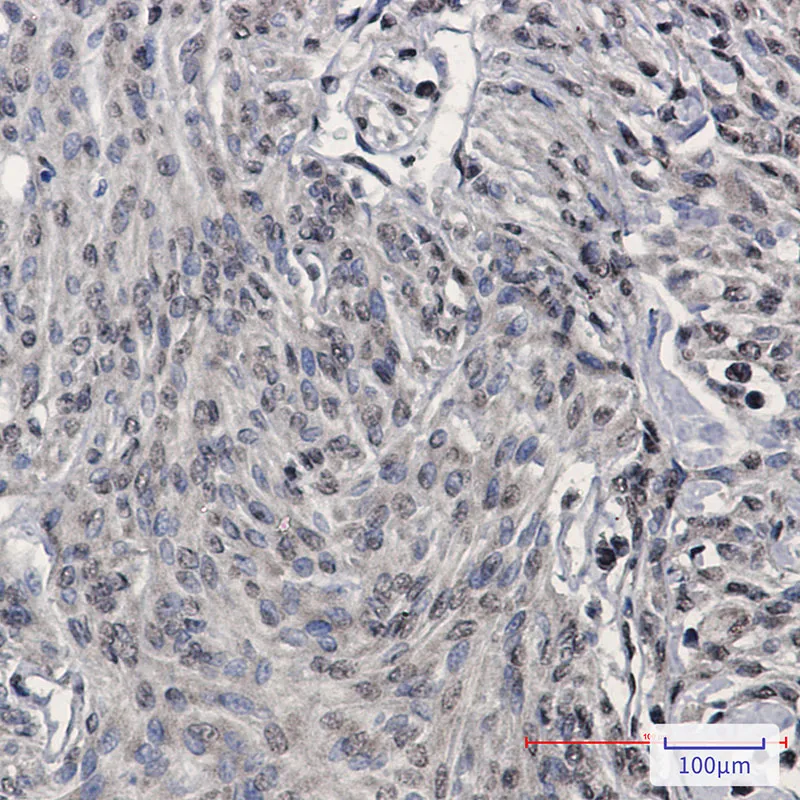

Immunohistochemistry analysis of paraffin-embedded Human brain using TDP 43 antibody.High-pressure and temperature Sodium Citrate pH 6.0 was used for antigen retrieval.